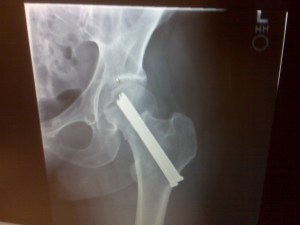

Studies found little, if any, benefit in reducing fractures after taking bisphosphonates (a class of osteoporosis medicine) for more than five years.

Furthermore, oral bisphosphonate use for longer than five years is associated with significantly increased risk of “atypical hip and femur fractures.”